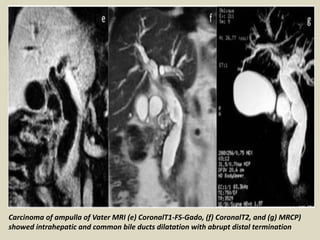

Carcinoma of ampulla of Vater MRI (e) CoronalT1-FS-Gado, (f) CoronalT2, and (g) MRCP)

showed intrahepatic and common bile ducts dilatation with abrupt distal termination

Carcinoma of ampullaof Vater MRI (e) CoronalT1-FS-Gado, (f) CoronalT2, and (g) MRCP) showed intrahepatic and common bile ducts dilatation with abrupt distal termination